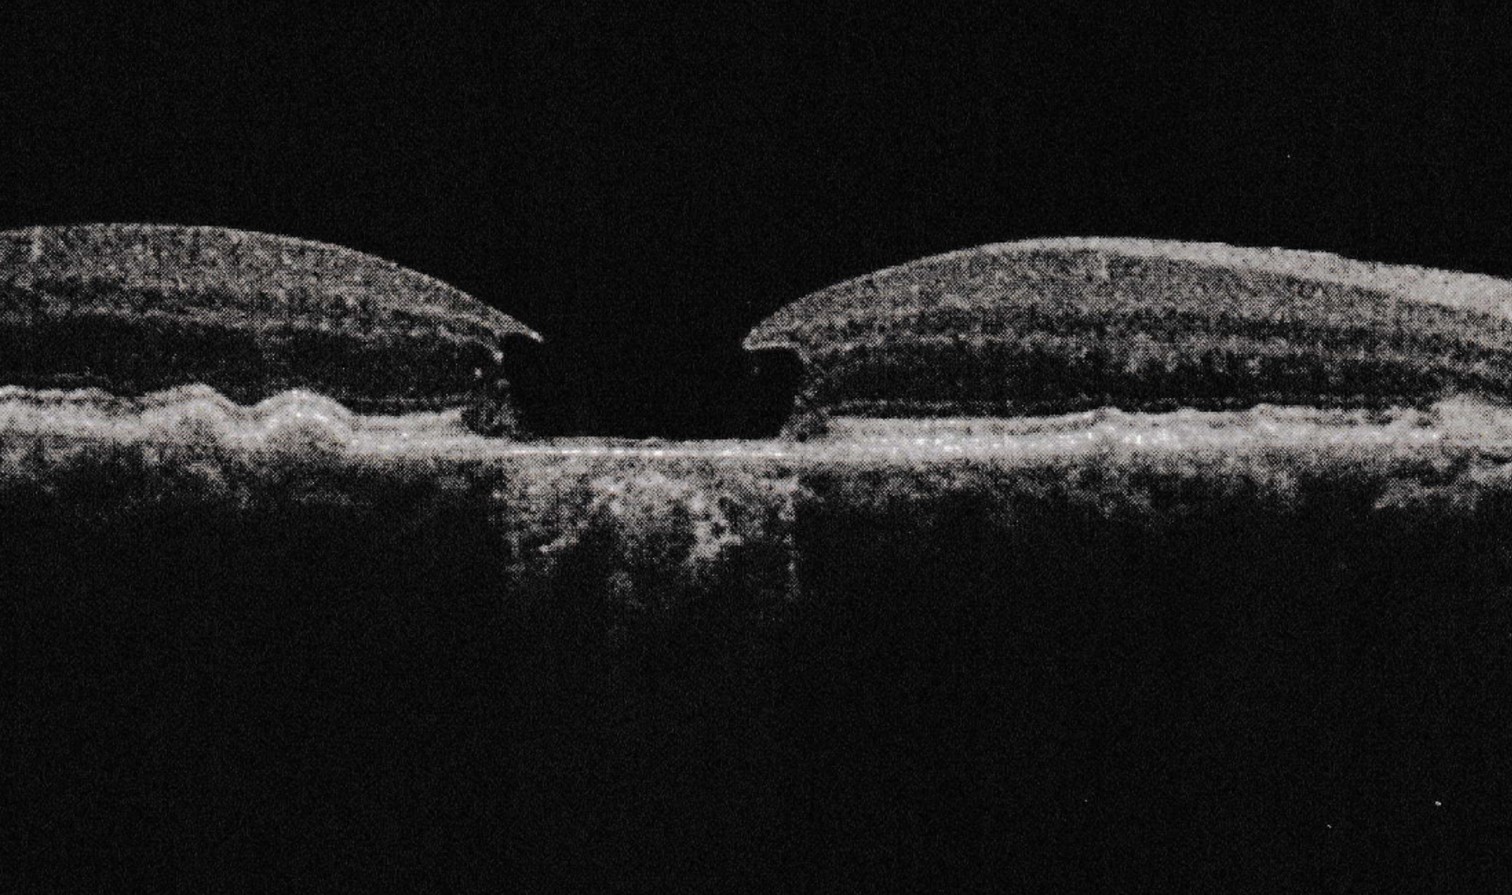

I remember the first moment when

the ophthalmologist told me my macular

degeneration in one eye had gone

from dry to wet. I probably felt momentary fear.

I had read enough to know that when one eye

goes, there is a fair likelihood the other

will eventually follow, and wet AMD

generally results in blindness.

I have lost central vision in that eye